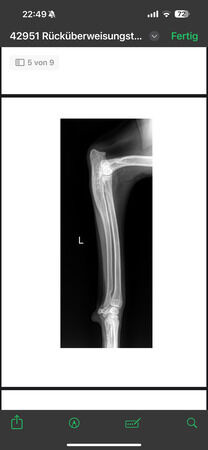

steht vorne sehr breit/ O-beinig, hi. re. Mitte Unterschenkel amputiert,

radiologisch kein Kniegelenkserguß oder Arthrose, nur Weichteilschwellung im Bereich distaler

Patellasehne, Elle proximal verdickt und Fehlstellung (alte, verheilte Fraktur?), keine deutlich

Ellbogenarthrose, leichtgradige Fehlstellung Unterarm li., auch leichtgradige Fehlstellung Radius re.

Alle Gelenke sonst ohne deutliche Arthrosezeichen.